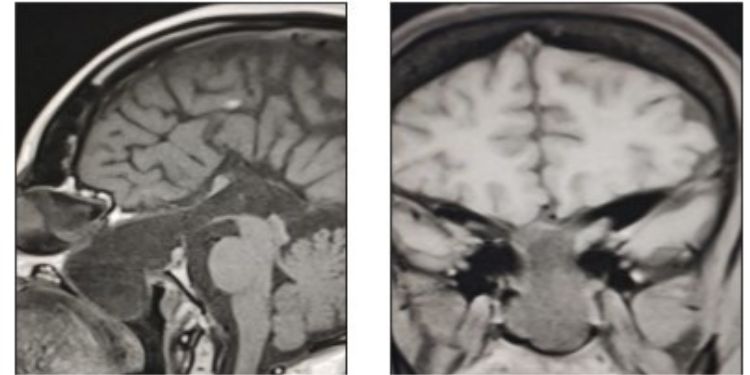

Article: A Treatable Cause of Progressive Visual Loss

A Treatable Cause of Progressive Visual Loss

Published on 18 Dec 2023